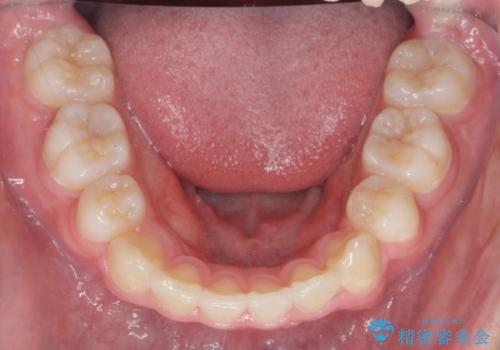

噛み締めが強く、治療に時間がかかりましたが矯正治療の仕上がりに満足いただくことができました。